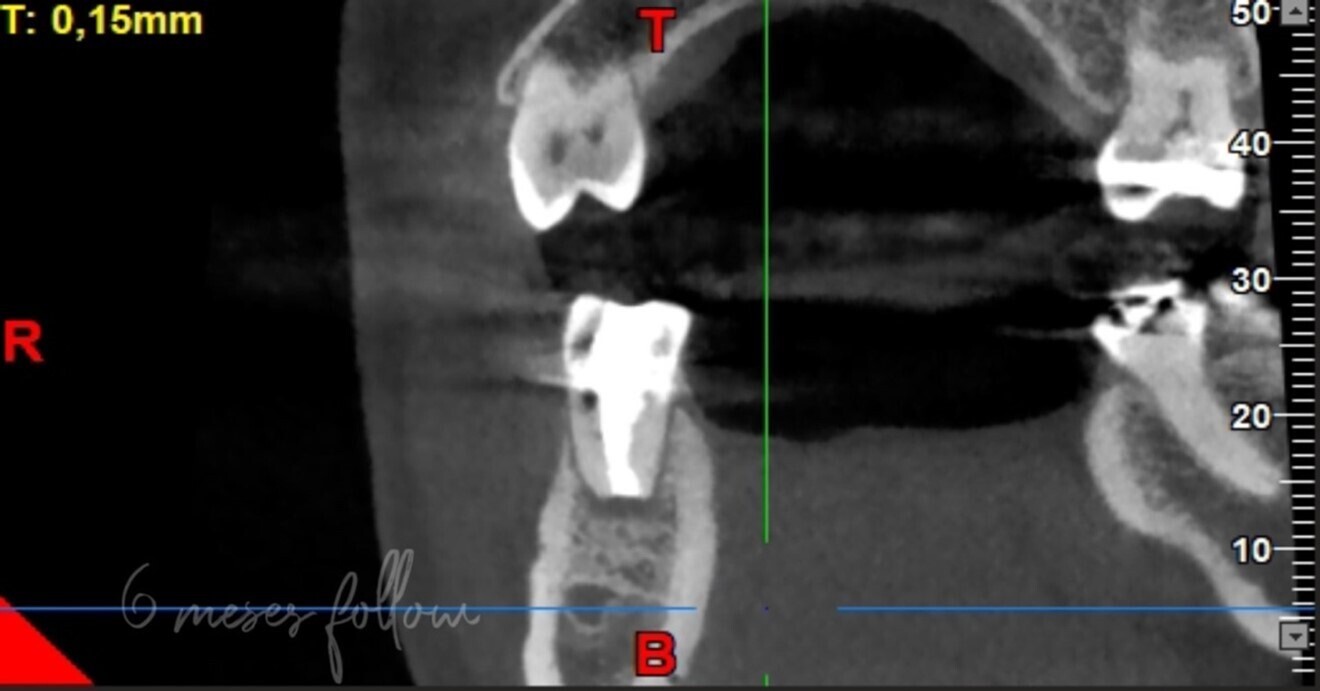

The radiographic examination showed periapical radiolucency and a radiolucent lesion in the cervical area of the tooth (Figs. 1 & 2). To determine the extent and depth of the lesion, a CBCT scan was performed (Fig. 3). Based on the CBCT images and 3D reconstructions, a diagnosis of Heithersay Class III external cervical invasive root resorption (ECIR) was determined in an endodontically treated tooth with symptomatic periapical periodontitis. The patient was informed of the diagnosis, treatment plan alternatives and prognosis of the case.

Figs. 3a–d: 3D reconstruction of axial section showing extension in mesial-distal direction (a). 3D reconstruction of a sagittal section showing the lesion extension, buccal-palatal direction (b). Coronal section of CBCT showing the extension of the periapical lesion and the resorptive defect (c). CBCT scan (d).

CBCT is a useful tool in endodontics, being used to assess the extent of an external cervical resorption defect, to detect and classify periapical periodontitis and to assess anatomical references with greater accuracy. Various studies have proved that CBCT is very helpful in diagnosis of this type of resorption.2–4 In the clinical case presented, an apical lesion and ECIR were observed, and CBCT was used to observe the size of the periapical lesion and the size and location of the resorption defect at the three spatial levels.